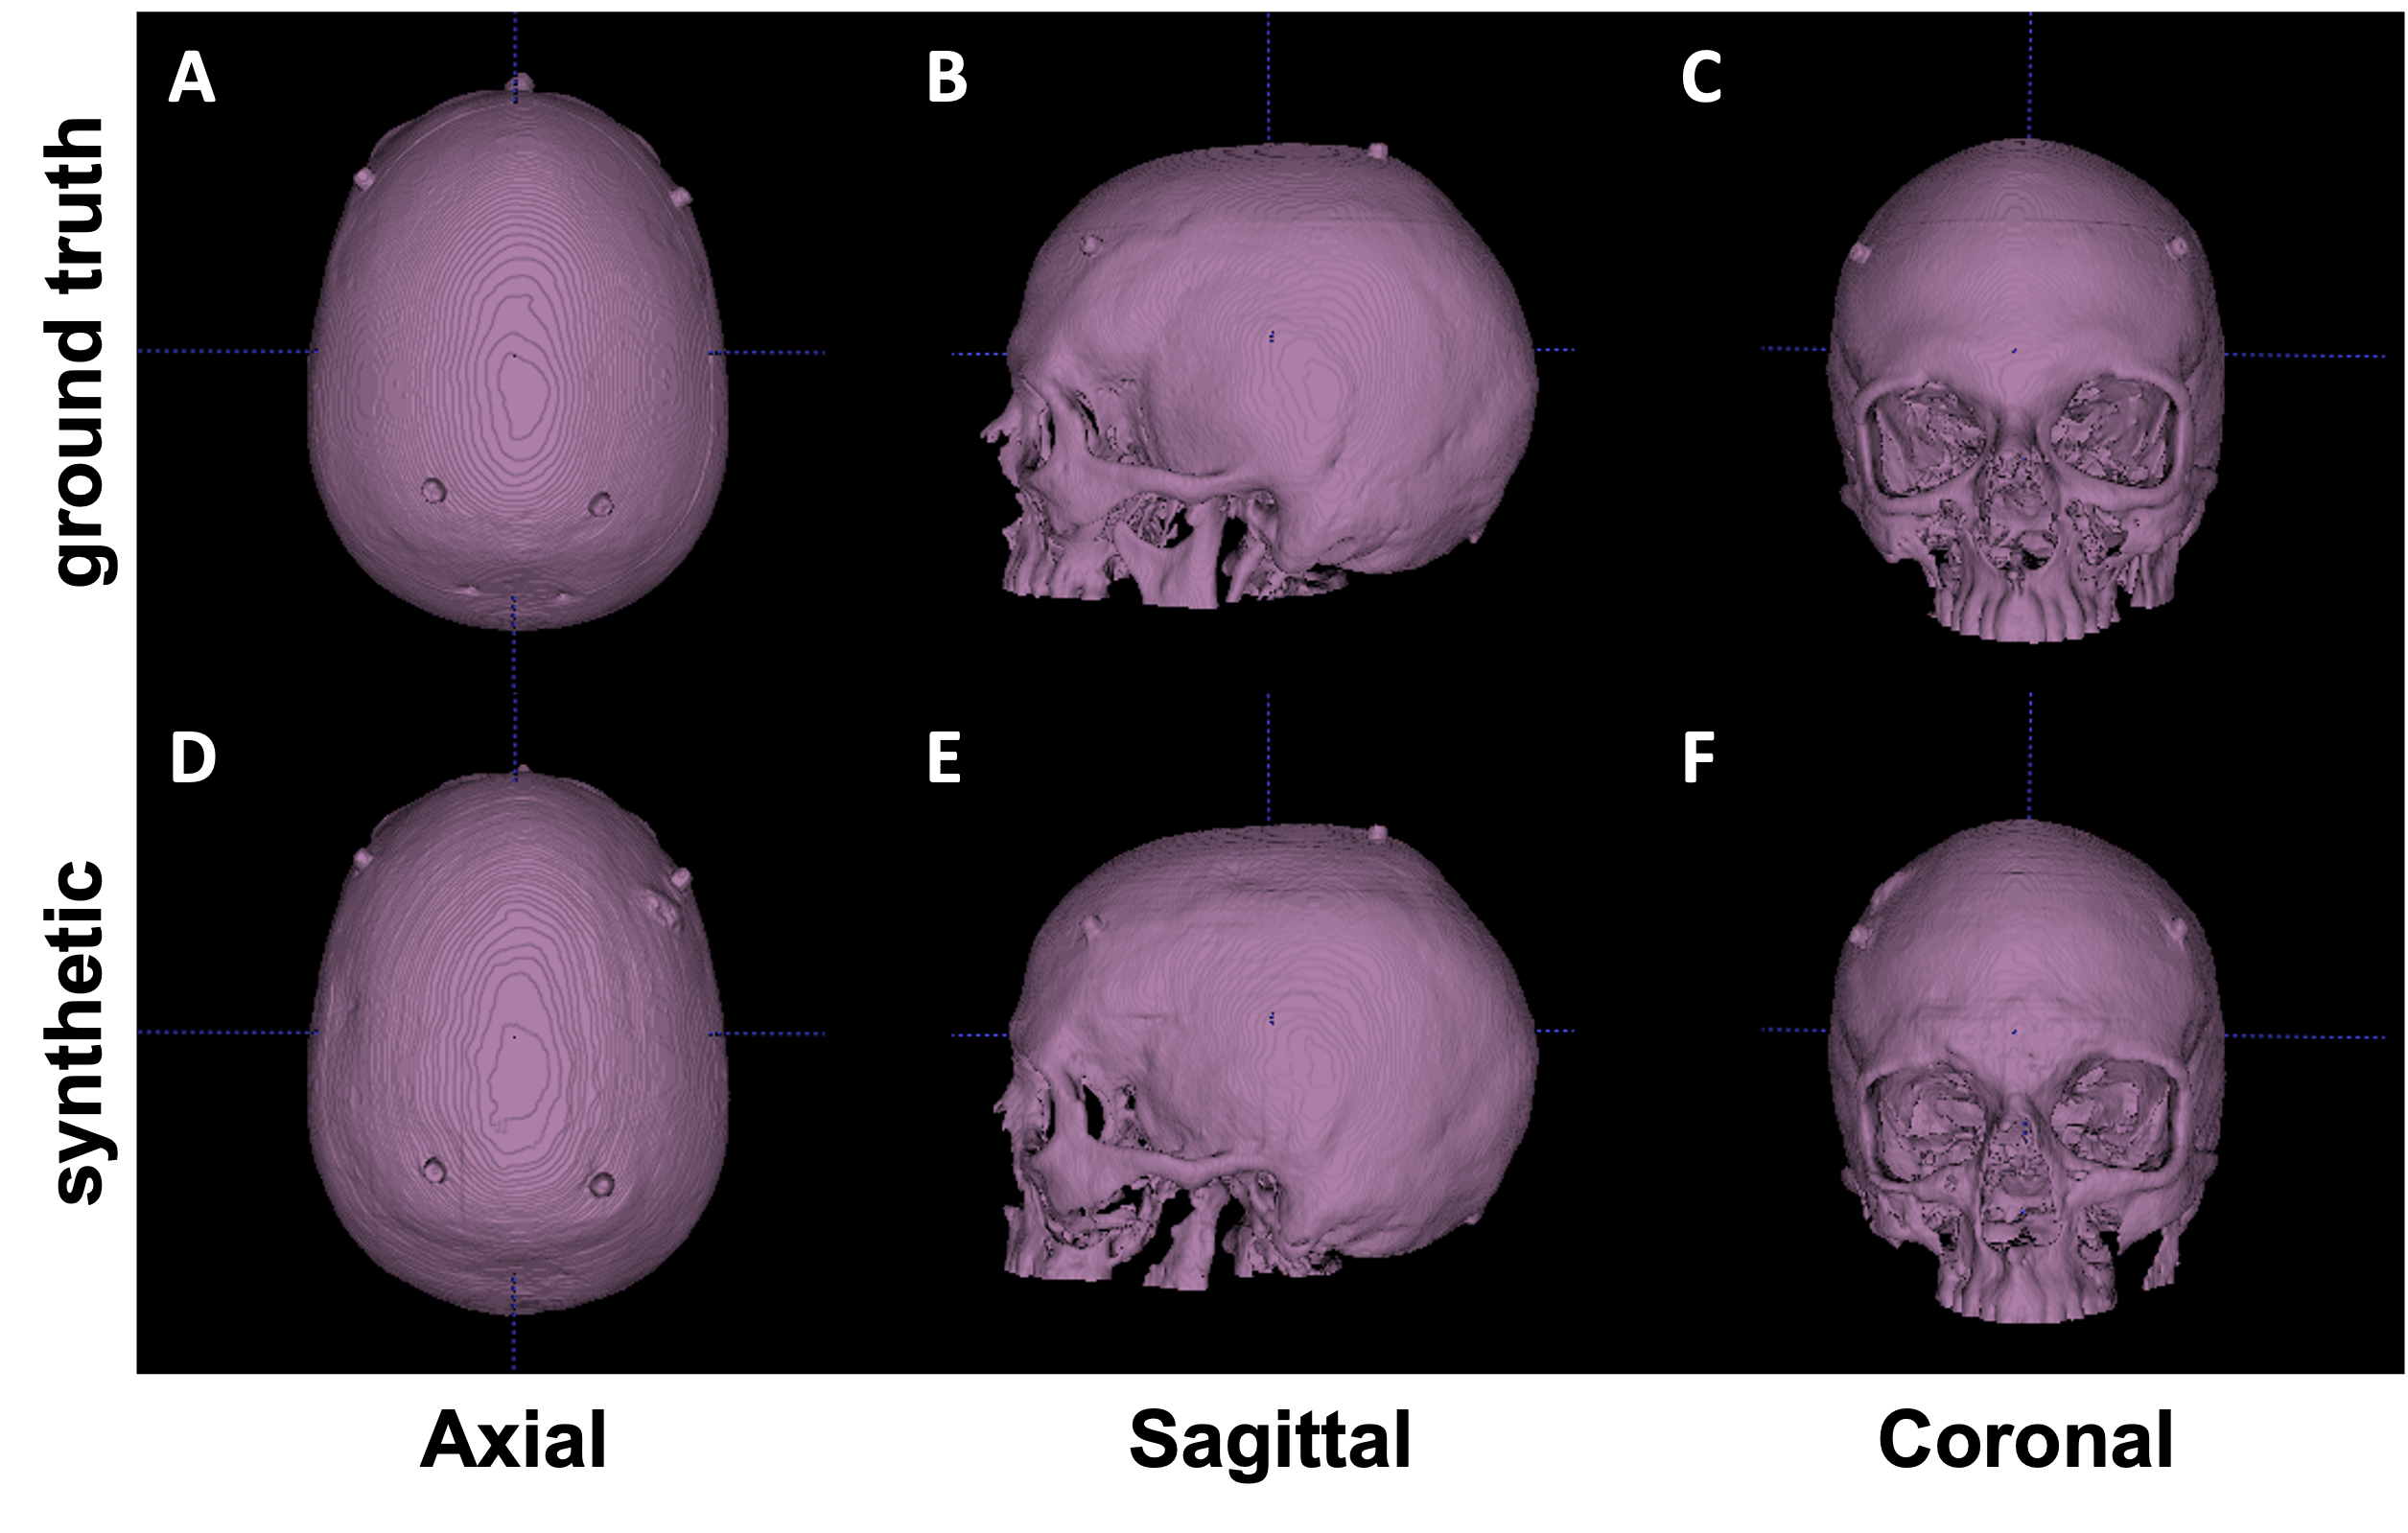

We performed both quantitative and qualitative evaluations of image similarity on our testing set. Quantitatively, we showed the box and whisker plot in Fig 1. Specifically, the MAEs between rCTs and sCTs in skull regions were 192.31±28.21plus-or-minus192.3128.21192.31\pm 28.21 HU and 206.83±27.91plus-or-minus206.8327.91206.83\pm 27.91 for cGAN and autoencoder, respectively. We performed paired t-test and found that the difference in mean MAE was statistically significant (p-value <0.01absent0.01<0.01). Qualitatively, as shown in Fig 2, we found that at the inferior part of the skull, the synthesized skull exhibited larger difference than at the superior part. The synthetic skull generated by cGAN also included more details and had sharper appearances compared to the one generated by autoencoder. Lastly, we note that our synthesized skulls were spatially continuous in all views and highly comparable to real skulls, as shown in Fig 3.

Refer to caption

Figure 3: Visual comparison between real (upper row) and synthetic (lower row) skull. Isosurfaces emphasize that synthetic CTs are visually comparable to real CTs and contiguous.